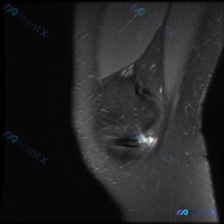

今天碰到一个有意思的病例,临床问的是有没有半月板异常,结果读片发现完全是另一个方向,整理一下整个分析过程跟大家分享。 病例影像基本信息 这是一张膝关节MRI矢状位T2加权抑脂图像,我们先整理一下影像所见: 1. 序列与解剖:矢状位显示髌骨、髌腱、髌下脂肪垫、股骨远端和胫骨近端,本次提供的单张图像层面...